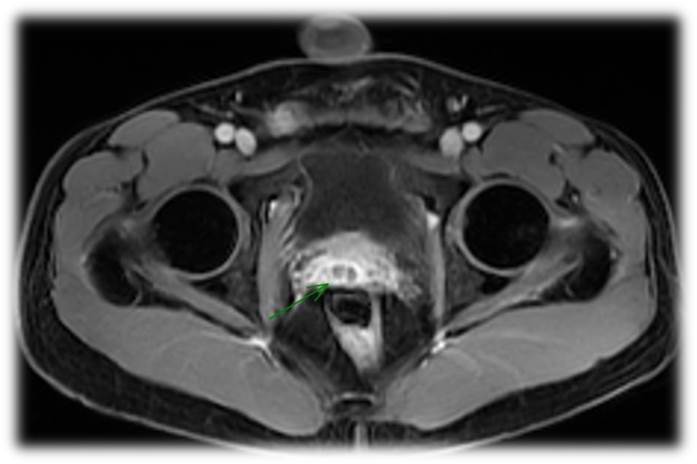

• Encaminhado por aumento do volume testicular e dor em região escrotal à direita há 3 meses

• Presença de nódulo endurecido na região inferior abaixo do testículo direito, porém, sem plano de clivagem à palpação

Características de imagem sugestivas de TB

• Aumento heterogêneo do epidídimo (principalmente cauda) associado a lesão testicular;

• Calcificação da túnica albugínea;

• Acometimento concomitante de outras estruturas do trato urogenital.